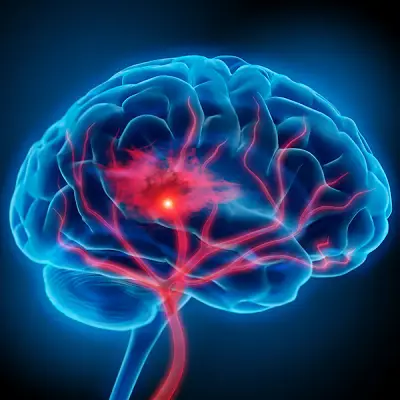

Paralysis Managenip Program

DBS

Microneurosurgery

Spine Surgery